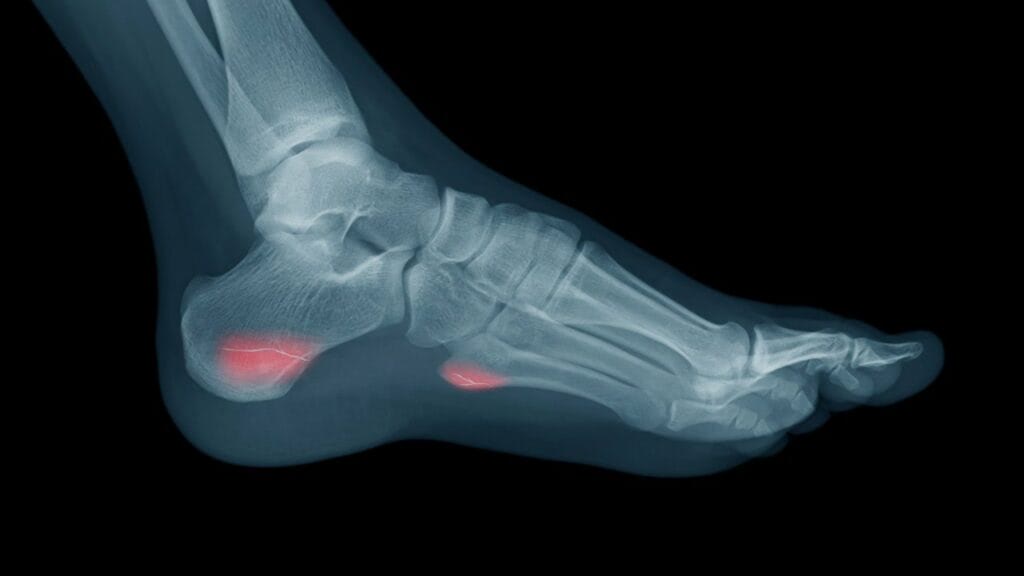

A stress fracture is a small crack (microdamage) in the bone that can occur from overuse or repetitive stress. The crack may not be visible on an x-ray initially and may only show up as a small area of increased density. If the stress fracture is left untreated, it can progress to a complete break in the bone.

Stress fractures are frequently seen in long-distance runners. Between one third and two thirds of competitive runners have a history of BSI, and the recurrence rate is high, with 10.3% to 12.6% of runners who have had BSI sustaining a subsequent BSI when followed for 1 to 2 years. BSI typically occurs in the tibial diaphysis (the long, narrow middle section of the tibia, or shinbone), with the majority of other BSIs occurring in the femur, fibula, calcaneus, metatarsals, and tarsals, but can occur in any bone region.

A systematic review looked at different ways of using imaging to diagnose lower extremity stress fractures and to recommend the best way based on the available evidence. The best way to diagnose stress fractures according to this review is through MRI, which is more accurate than other methods, including x-rays, and does not involve exposure to ionizing radiation. CT is not as good as MRI, but it is better than x-rays. Bone scan are useful for excluding a stress fracture but not for diagnosing one. Below is a treatment algorithm that was suggested by the researchers.